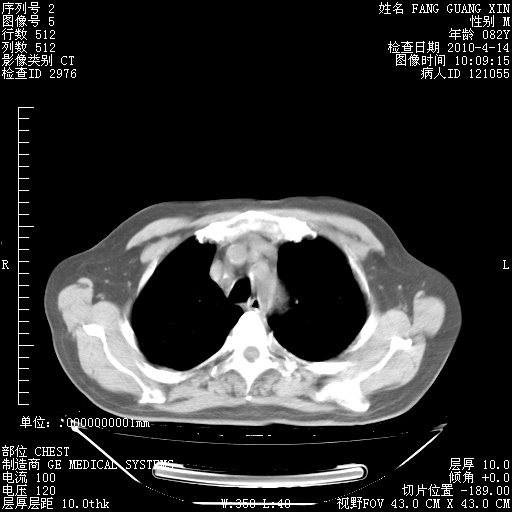

4月14日肺部CT

肺部CT平扫未见异常。